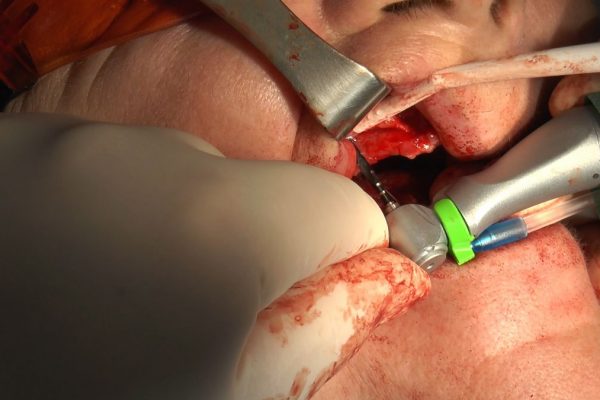

W ostatni weekend czerwca 2018 roku kursanci II Sezonu Preludium Implantologii odbyli piątą, finałową sesję, która w całości podporządkowana była praktyce. W ciągu dwóch dni zabiegowych Lekarze uczestniczący w szkoleniu przeprowadzili szereg zabiegów pod kierunkiem dr n.med. Violetty Szycik. Wszczepili 17 implantów oraz przeprowadzili ekstrakcje i zabiegi regeneracyjne kości. Zabiegi były wykonywane także w sedacji dożylnej z udziałem specjalisty anestezjologii i intensywnej terapii dr Jolanty Grzybowskiej. Preludium implantologii to nowy program edukacyjny dla adeptów implantologii stomatologicznej, którego celem jest wprowadzenie do implantologii poprzez pozyskanie wiedzy w szerokim zakresie i uwzględnieniem szczegółów mających decydujące znaczenie dla powodzenia leczenia implantologicznego. Ale tak jak wszystkie szkolenia w Instytucie Vivadental, w tym wiodące Practiculum Implantologii, zorientowane jest na praktyce i samodzielnym wykonywaniu zabiegów pod kierunkiem Mentora. To najlepsza edukacja w medycynie zabiegowej, a zarazem najlepszy start do implantologii.